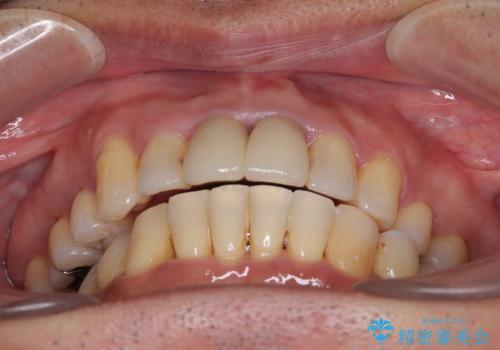

- 八重歯を気にして来院された患者様です。

上顎前歯の突出感と右上の八重歯を気にされていたので、上顎左右の第一小臼歯2本を抜歯し、ワイヤー装置にて矯正治療を行うこととしました。

上顎前歯に装着されていた保険診療の前歯は見た目が気になるとのことであったので、矯正治療後にオールセラミッククラウンにて補綴治療を行うこととしました。

食いしばりにより奥歯がすり減っており、咬み合わせが定まるまで時間がかかりましたが、整った口もに仕上がりました。